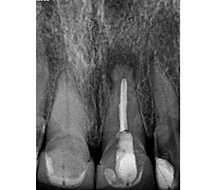

• 本产品可与种植体接触使用。一旦新骨生长完成,可将种植体植入新骨中,完成植入过程。

对标全球牙科领导者Bio-Oss(牛源),CoreBone是更优的选择